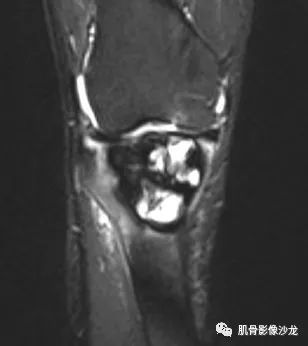

右胫骨骨巨细胞瘤1例MR

男,58岁,右膝疼痛不适,逐渐加重。